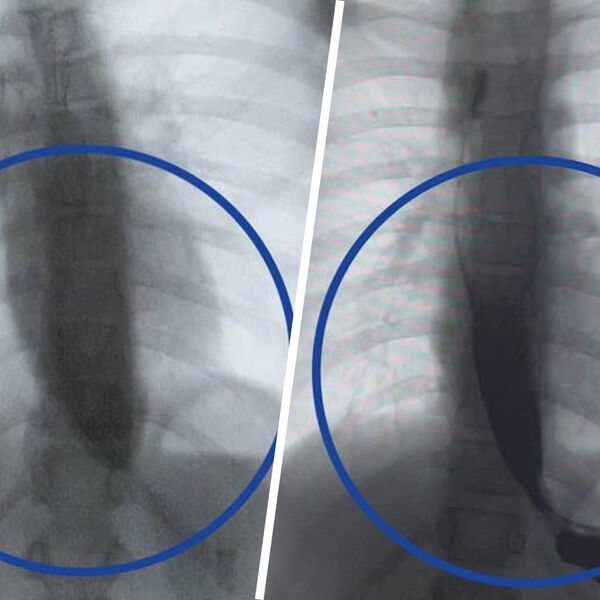

Врачи Детского клинического центра им. Л.М. Рошаля спасли девятилетнюю девочку с редким заболеванием — ахалазией кардии, из-за которого ее пищевод был расширен в пять раз. Об этом сообщили в пресс-службе минздрава Московской области.

Медики рассказали, что пищевод пациентки из-за патологии был расширен до четырех сантиметров, при норме в семь — десять миллиметров.

Операция прошла успешно, что уже на следующий день показало контрастное исследование — пища стала беспрепятственно поступать в желудок.